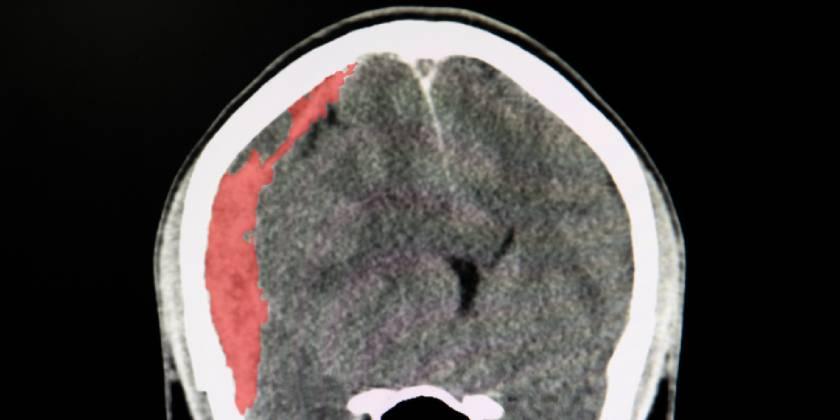

Eficacia y seguridad de la dexametasona en el hematoma subdural crónico

17 diciembre 2020

Un ensayo clínico mostró que el corticoide se asoció a peores resultados clínicos a los seis meses en comparación con placebo, pero con menor cantidad reoperaciones. New England Journal of Medicine, 16 de diciembre de 2020.